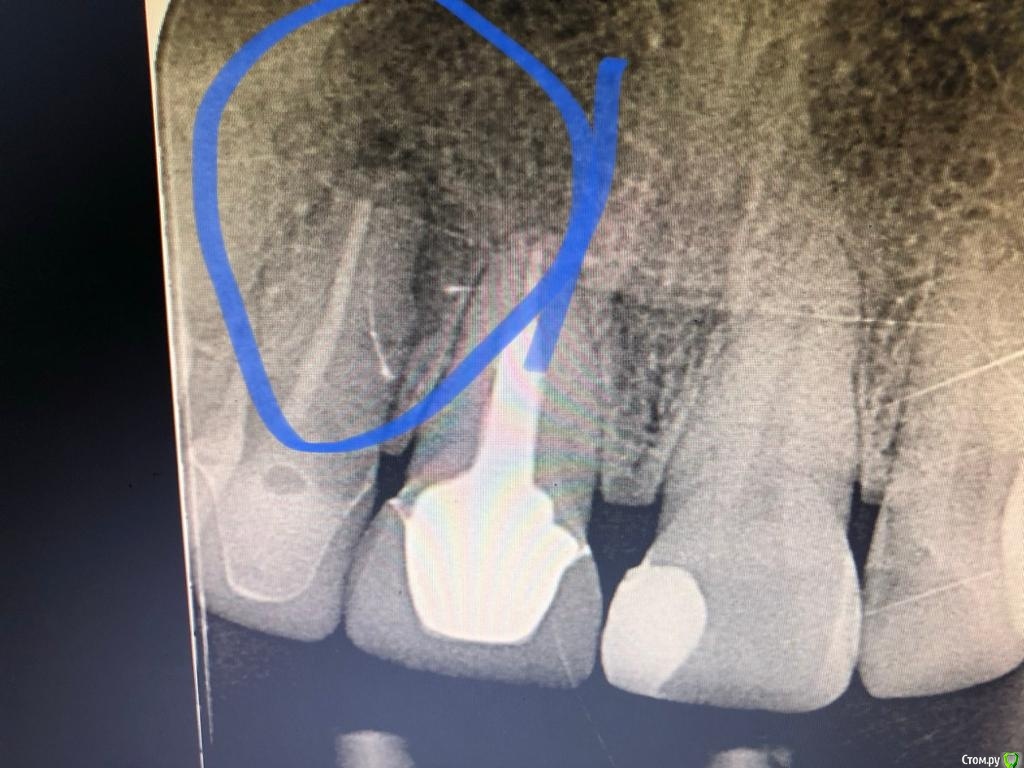

Лора777 Опубликовано 13 ноября, 2020 Автор Поделиться Опубликовано 13 ноября, 2020 Здравствуйте!Клкт посмотрите пожалуйста Ссылка на комментарий

Лора777 Опубликовано 13 ноября, 2020 Автор Поделиться Опубликовано 13 ноября, 2020 Клкт Ссылка на комментарий

Nazim_NV86 Опубликовано 13 ноября, 2020 Поделиться Опубликовано 13 ноября, 2020 До полости носа и синуса далеко. Изменения небольшие. Не вижу состояния синуса. покажите КЛКТ лору. Не можем ответить на вопрос об аллергии, т.к. нет данных про то, ложили что-то туда или нет( а если узнаем, то проверять наличие аллергии у аллерголога). Если этот зуб и виновен в рините, то только рефлекторно. Проверить это можно только его удалением (к сожалению). Ссылка на комментарий

Bier Опубликовано 16 ноября, 2020 Поделиться Опубликовано 16 ноября, 2020 там рецидив однозначно, связан с отсутствием ретроградной пломбировки канала. Ссылка на комментарий

annda Опубликовано 19 ноября, 2020 Поделиться Опубликовано 19 ноября, 2020 На джи- дефект похоже. Пусть связку по кругу прозондируют, нет ли узкого глубокого кармана, трещину исключают. Ссылка на комментарий